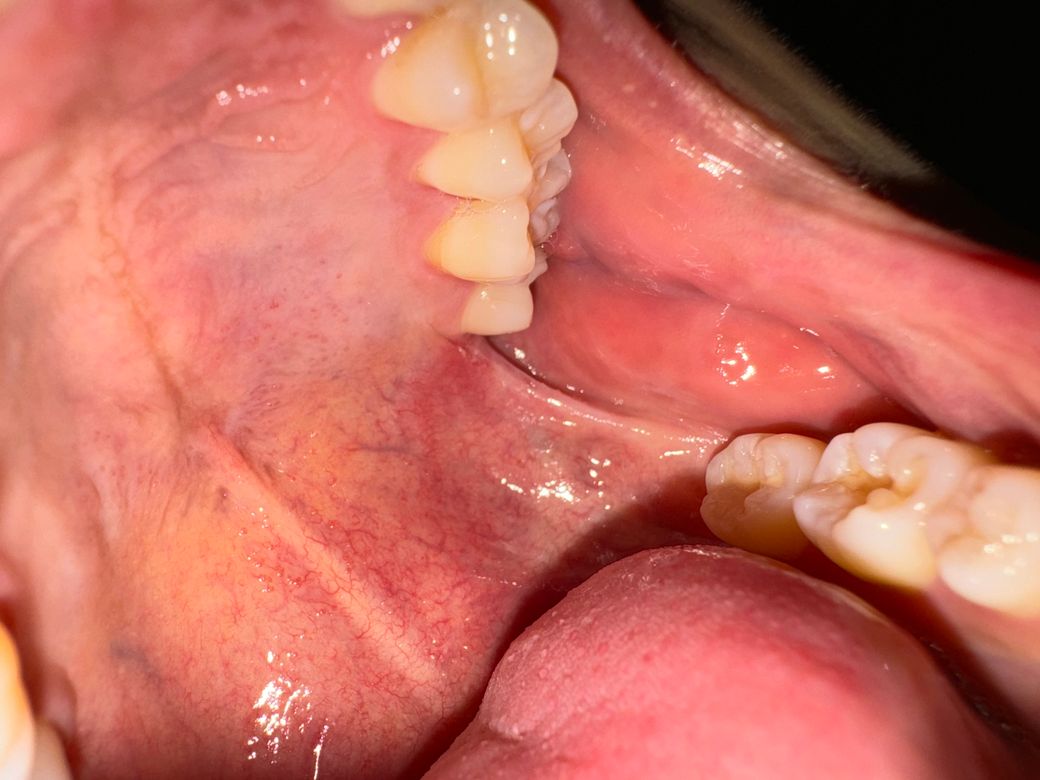

왼쪽 위 어금니 뒤 사랑니 나는 자리에 상처가 나있어요

5개월 전에 충치 땜빵할게 있어서 치과갔을 때 입을 크게 벌리면서 익돌하악봉선이 갑자기 엄청 땡기면서 그 부분이 찢어지고 상처가 났었는데 거기랑 이어지는 어금니 뒤쪽 사랑니 나는 자리에 흰색 뾰루지같은게 세개정도 나있어요. 크게 아프진 않고 신경 쓰일 정도로 쓰라린 정도인데 뭘까요? 한 3일정도 됐고 익돌 하악봉선쪽에 찢어진건 5개월 됐습니다. 두달정도 전에 치과갔을 때는 구강암같은건 아니라고하시고 연고 주셔서 며칠 바르니까 완치는 아니고 거의 나았었는데 이게 또 재발한걸까요? 사진상으로 심각한 병으로 보이시나요? (참고로 저 부위에는 사랑니가 없습니다.)

• 2번 째 사진

사진상 봤을때는 특별히 악성 병소의 양상은 아니나 정확한 검사를 위해서는 대학병원의 구강내과에서 조직검사를 해보면 좋을 것 같습니다.